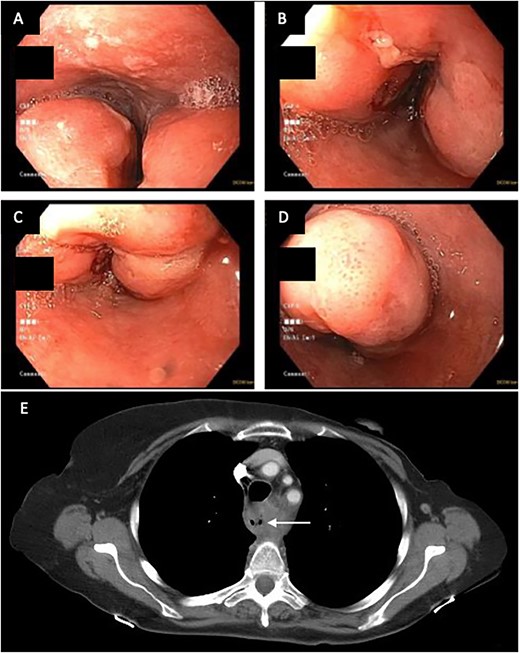

In April of 2022, the patient developed recurrent pneumonias, hemoptysis, and progressive dyspnea, raising concern of tumor invasion into the airway. Bronchoscopy confirmed a large tumor encompassing 2/3 of the airway, with evidence of stent erosion through the trachea (August 2022, Fig. 3). Laser debridement of the tumor was successfully performed.

Bronchoscopic evidence of tumor growth into the trachea with evidence of stent erosion (August 2022).